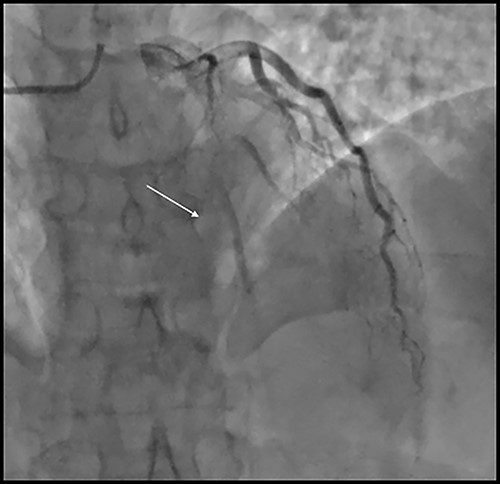

A 38-year-old man known case of hyperlipidemia, hypertension and ET diagnosed 5 years previously by bone marrow biopsy with JAK2 mutation (Janus Kinase 2) presented with angina. He was on hydroxy urea therapy since that time. He underwent multiple percutaneous coronary interventions to left anterior descending artery (LAD) and first diagonal artery (D1) for past 5 years. He presented with unstable angina. He had no past surgical history and no family history of ischemic heart disease. He was non-smoker. Coronary angiography showed total occlusion of LAD and D1 arteries with normal right coronary and circumflex arteries (Fig. 1). Echocardiography showed ejection fraction of 50% with no significant valve disease. Hemoglobin was 16 g/l and platelet count was 495 * 109 per litter with normal renal and liver function tests. His hydroxyurea medication was continued at a dose of 500 mg orally daily until day of surgery.

Coronary angiography showing subtotal occlusion of the LAD stent and severe in stent re stenosis of diagonal artery stent.